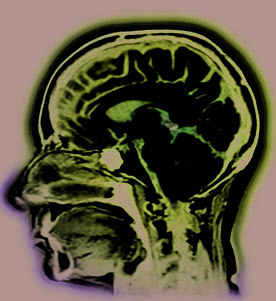

Side View of the Brain

This illustration shows a three-dimensional side

view of one of two cerebral hemispheres of the brain.

To help visualize this, imagine looking at the cut side

of an avocado sliced long ways in half, with the

pit still in the fruit. In this illustration, the “pit” is

several key structures that lie deep within the brain

(the hypothalamus, amygdala, and hippocampus)

and the brain stem.